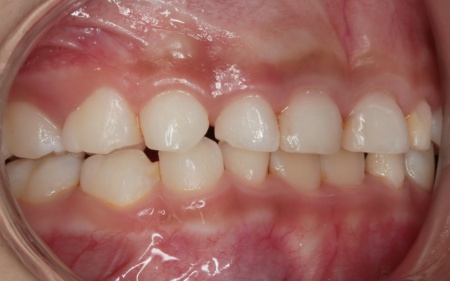

治療後

治療中は、スクリューを少しずつ回すことで顎の骨が徐々に横方向に拡大されていき、永久歯が生えるためのスペースを十分に確保することができました。

拡大治療が完了したあとは、顎の状態を安定させるためのリテーナー(保定装置)を装着し、治療を終了しています。